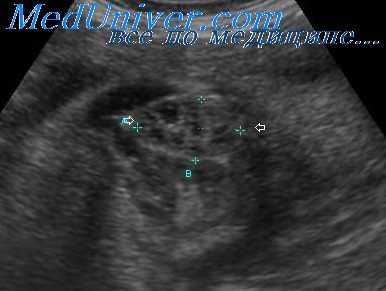

При ультразвуковом исследовании признаком удвоения может служить обнаружение гидронефроза, изолированно поражающего только верхние или нижние отделы почки. Чаще всего гидронефроз ограничен верхними отделами почки или имеет там большую выраженность. В связи с этим может визуализироваться сопутствующее расширение верхнего мочеточника, а в ряде случаев обнаруживаться эктопическое уретероцеле, пролабирующее в просвет мочевого пузыря.

Дилатация собирательной системы верхних отделов почки может создавать впечателение наличия кистозного изменения или гидронефроза всей почки.